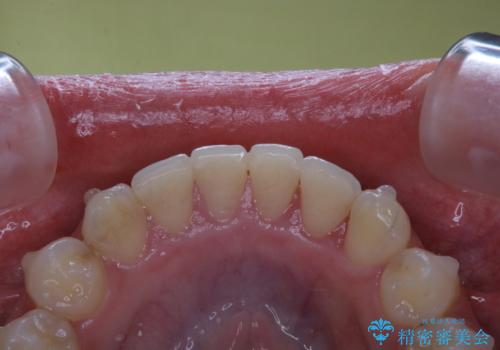

インビザライン中にステインの除去

- インビザラインでのマウスピース矯正中の方で、歯の表面のステインをきれいに取りたいとのことでした。PMTC60分コースを行いました。

PMTC(保険外治療)は、毎日の歯磨きで落としきれない汚れや、コーヒ、紅茶・タバコのヤニなどの着色も除去します。目には見えない歯と歯の間・歯肉の境目・インビザライン中はアタッチメント周囲などに残っているプラーク(歯垢)もしっかり取り除きます。PMTCでは専門的な機械や材料を使用して、徹底的に汚れを除去するため、虫歯・歯周病・口臭予防などにつながります。